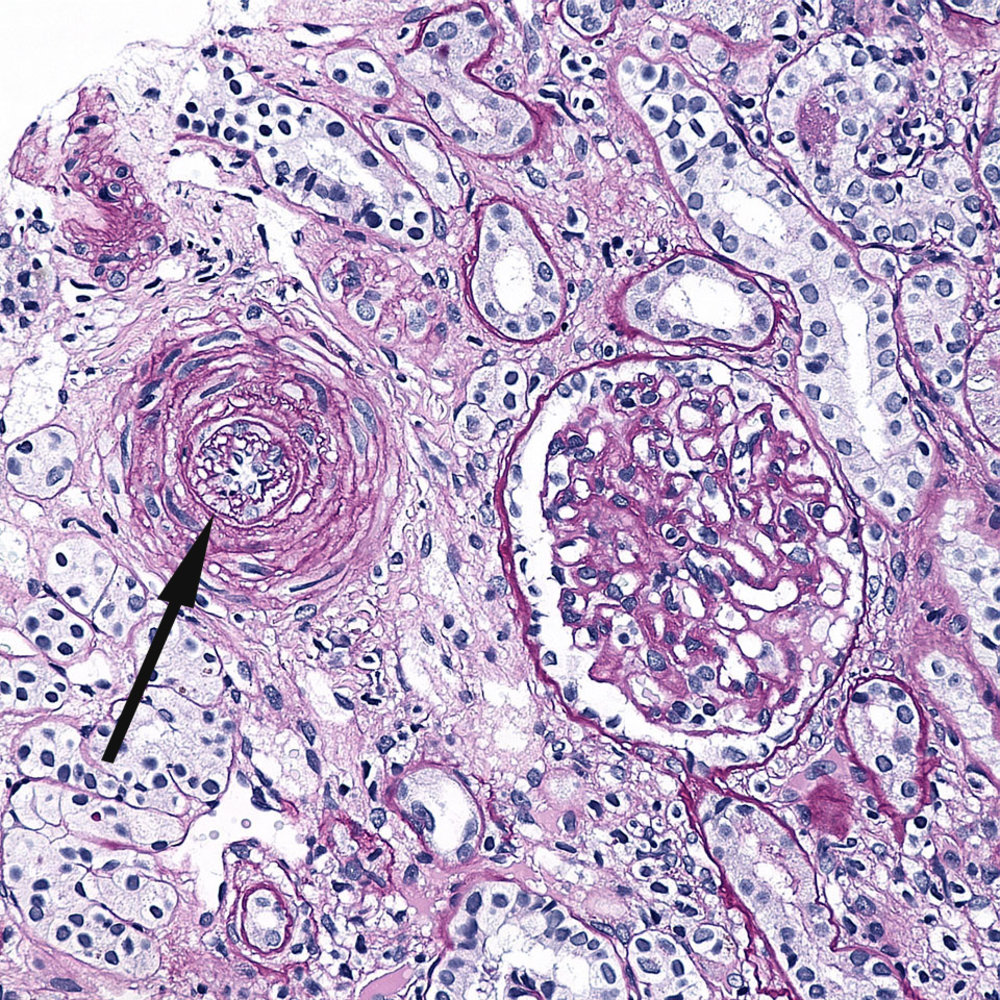

Hyaline arteriolosclerosis

- Deposition of proteins below the endothelium due to plasma protein leakage

- H&E: pink amorphous deposits (hyaline) within the arteriolar walls

- Causes: chronic essential hypertension, diabetes mellitus, and normal aging